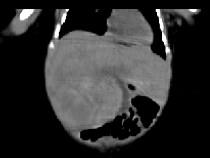

男,5天,上腹部膨隆,CT所见如图,最可能的诊断是()A.原发性肝癌B.肝母细胞瘤C.肝血管瘤D.肝脓肿E.肝转移瘤

问题 男,5天,上腹部膨隆,CT所见如图,最可能的诊断是()

选项 A.原发性肝癌 B.肝母细胞瘤 C.肝血管瘤 D.肝脓肿 E.肝转移瘤

答案 B